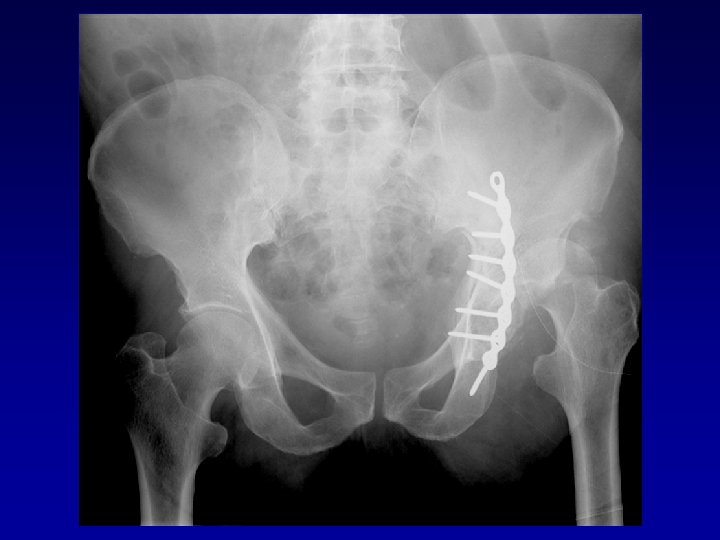

Déformation du cotyle • Ascensionné • Perte de substance osseuse scanner • Pseudarthrose •

Déformation du cotyle • Ascensionné • Perte de substance osseuse scanner • Pseudarthrose • Perte du positionnement exact (idem LCH) • Doit être reconstruit et recentré

Chirurgie préalable Le matériel en place • Gêne le creusement, la reconstruction Les complications

Chirurgie préalable Le matériel en place • Gêne le creusement, la reconstruction Les complications • Nerveuses : sciatique, crural, fessiers (EMG) • Infectieuses

Arthroplastie totale de hanche sur fracture du cotyle complexe Recentrage, reconstruction, orientation du cotyle • • Greffe Ostéosynthèse par plaque MK Surtout si pseudarthrose Réduction de la luxation